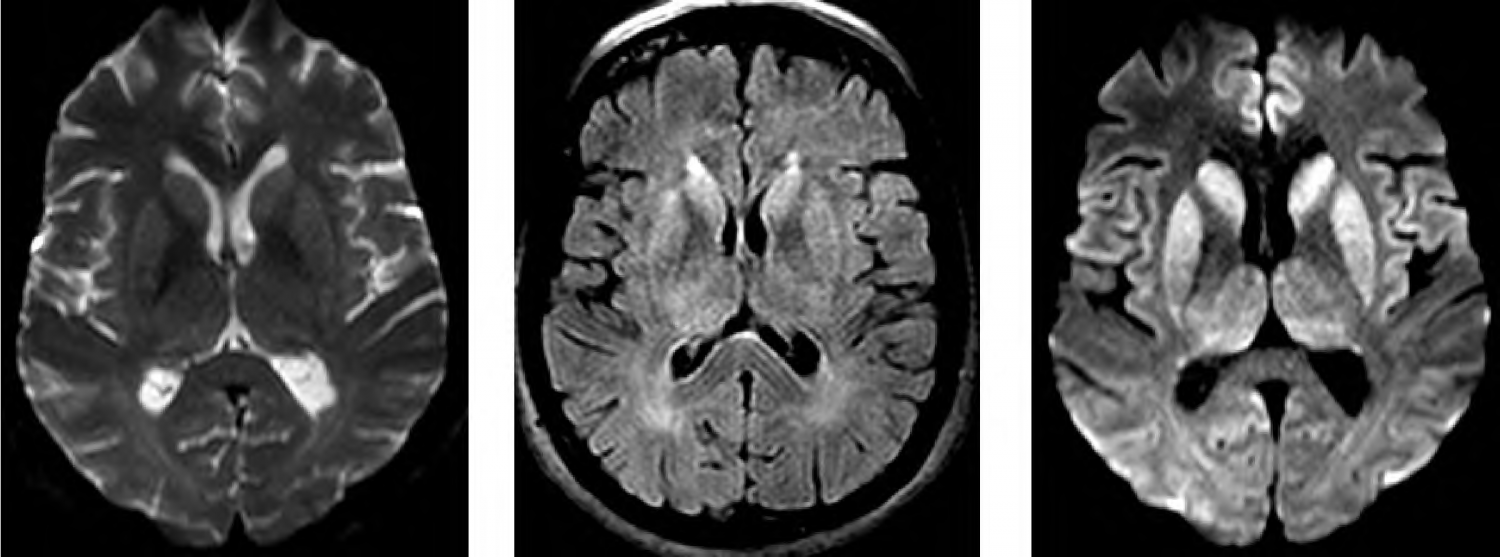

J.P, 58 anos, foi levado ao hospital com prejuízo cognitivo de início há 3 meses, com evolução progressiva, envolvendo atenção, praxia, planejamento, orientação temporoespacial, função executiva e memória. Realizado miniexame do estado mental com 12/30 pontos. Avaliação funcional evidenciou prejuízos significativos de atividades instrumentais e básicas de vida diária. A família relata que há 6 meses vem apresentando desequilíbrio e quedas frequentes. O exame neurológico revelou presença de mioclonias frente a estímulos sensoriais. Os exames de sangue gerais solicitados vieram dentro do padrão de normalidade, descartando infecções ou distúrbios hidroeletrolíticos. EEG demonstrou padrão periódico de ondas trifásicas sobre atividade de fundo atenuada. Realizou exame de ressonância de crânio (T2, FLAIR e DWI) que mostrou as seguintes imagens:

De acordo com a imagem apresentada no caso clínico, o principal achado que auxiliaria a confirmação diagnóstica é:

No exame de líquor, o teste a ser pedido e que é um importante biomarcador para a confirmação diagnóstica é:

O diagnóstico mais provável do presente quadro é